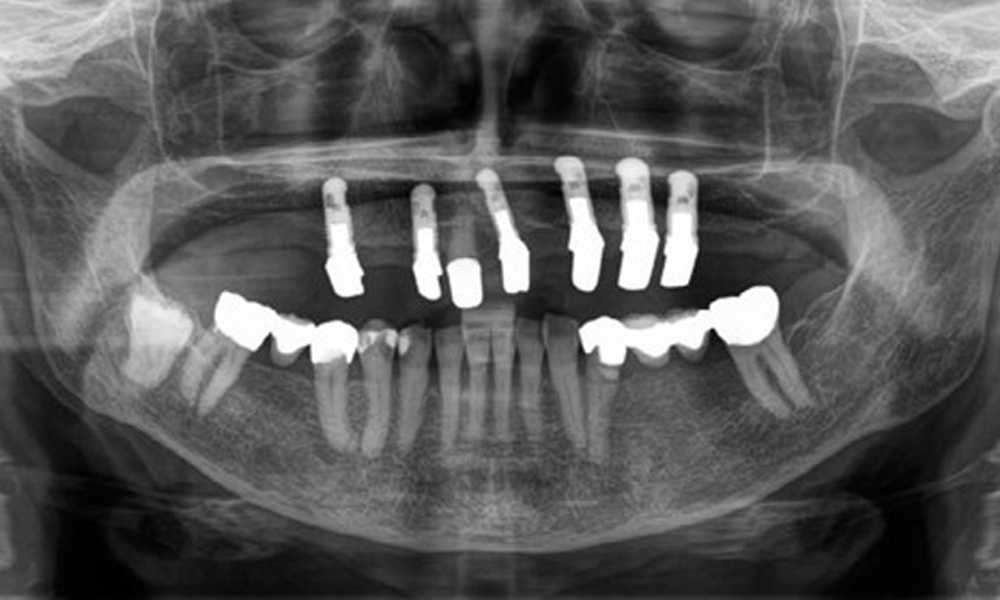

Die Patientin wurde vor über 25 Jahren mit einer kombinierten herausnehmbare Implantat-Teleskopprothese im Oberkiefer versorgt (Abb. 1, Abb. 2, Abb. 3) und ist sehr glücklich über ihren Zahnersatz. Im Unterkiefer hat die Patientin einen suffizienten festsitzenden Zahnersatz. (Abb. 4)

Der dentale Befund stellt sich wie folgt dar: Kombinierte herausnehmbare Implantat- und zahngetragene Teleskoparbeit auf Implantaten 15, 13, 21, 23, 24, 25 und Zahn 11 (Abb. 1, Abb. 2, Abb. 3). Im Unterkiefer ist die Patientin mit einem festsitzenden Zahnersatz versorgt. 37–34 sowie 45–47 haben suffiziente Brücken (Abb. 4). Kronenränder sind intakt, aktive kariöse Läsionen sind nicht vorhanden. An Zahn 43 zeigt sich eine Compositefüllung mit Randspalt. Im Unterkiefer liegen Rezessionen mit freiliegender Wurzeloberfläche zwischen 1 – 3 mm vor. Dies trifft auch für 11 zu.

Aus dem radiologischen Befund zeigt sich ein teilbezahntes Gebiss mit Implantaten im Oberkiefer an 15, 13, 21, 23, 24, 25 und einer Teleskopkrone 11. Im Unterkiefer sind suffiziente Brücken von 37–34 und 45–47 vorhanden. 48 ist retiniert. 43 distal besteht der Verdacht auf Sekundärkaries und 44 mesial Verdacht auf Sekundärkaries. 44 ist mit einer nicht röntgenopaken Unterfüllung versorgt.

Es zeigt sich ein generalisierter horizontaler Knochenabbau von ca. 10–30 % und lokalisiertem vertikalen Knochenverlust an 22 und 42. (Abb. 5)